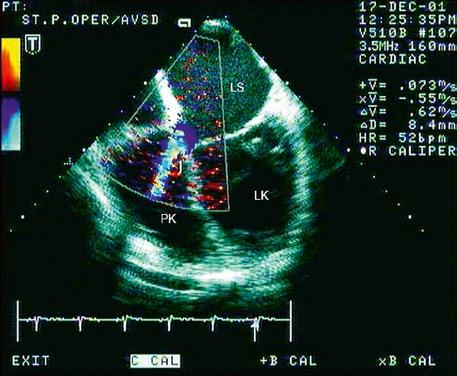

Obr. 45.14 TTE, čtyřdutinová apikální projekce. Kompletní atrioventrikulární septální defekt je označen křížky, představuje komunikaci mezi oběma síněmi i komorami se společnou atrioventrikulární chlopní (AVch)

LK – levá komora, LS – levá síň, PK – pravá komora, PS – pravá síň